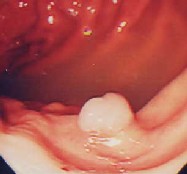

胃ポリープ:

健診の胃X線検査でポリープの疑い、内視鏡検査を施行すると小豆大の白色調の表面平滑なポリープを認めました。組織検査では過形成性ポリープの診断。このポリープは、大きくなったり癌になったりすることはありません。年に一度の検査で十分と思います。